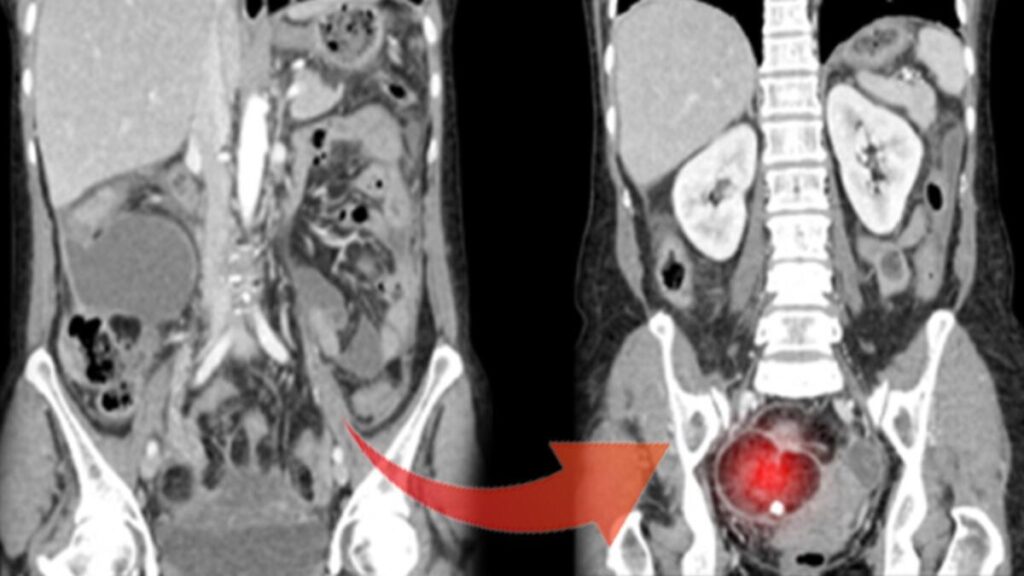

Şekil 1-Dermoid kistli yumurtalık Şekil 2-Normal yumurtalık